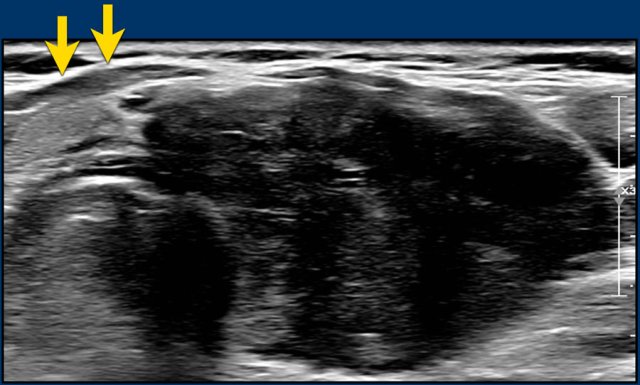

Very hypoechoic , i.e. 3 points in TI-RADS. Very hypoechoic , i.e. 3 points in TI-RADS.

A very hypoechoic lesion is more hypoechoic than normal muscle.

Notice that the tumor is more hypoechoic in comparison to the strap muscles (arrows).